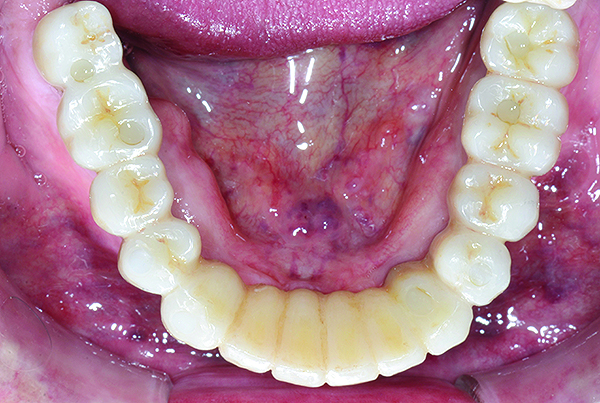

Upon completion of the above procedures, alginate impressions were made of the provisionals. Polyvinylsiloxane closed-tray transfer impressions were made of the maxillary and mandibular arches. The bite registration was obtained by transferring the provisionals to the master casts and mounted on an appropriate articulator. The provisionals and master casts were scanned into the digital environment for production of the maxillary and mandibular prototypes. The prototypes offer the advantage of being able to digitally correct minor design issues and then verifying and adjusting intraorally (Figure 7 through Figure 10).

Fig 9. Virtual design of mandibular prototype and definitive restoration, occlusal view (Fig 9) and intaglio view (Fig 10).

Figure 9

Fig 10. Virtual design of mandibular prototype and definitive restoration, occlusal view (Fig 9) and intaglio view (Fig 10).

Figure 10